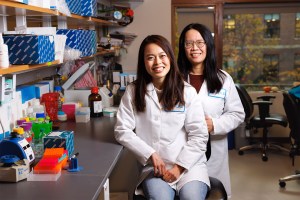

Science & Tech

Aramont Fellowships give scientists freedom to concentrate on high-risk, high-reward research

Renewed gift significantly expands the impact of early-career support

Science & Tech

Study suggests healing skin without scarring may be possible

Researchers unblock embryonic regrowth mechanism that shuts down after birth in mice